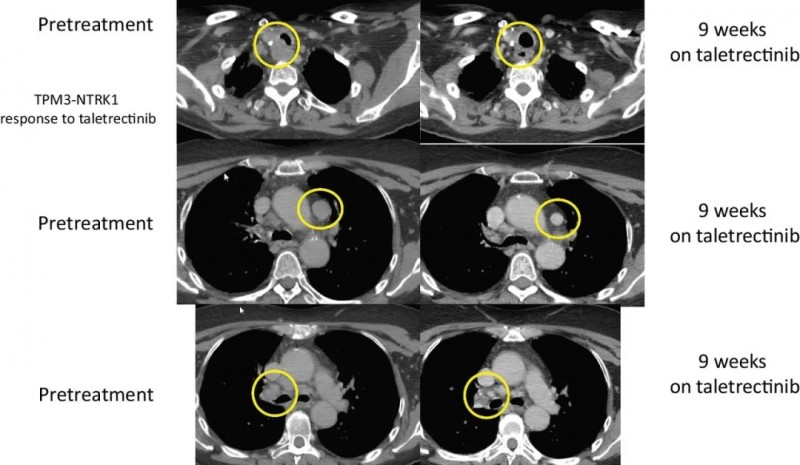

甲状腺癌:

另一位患者是晚期甲状腺癌,手术后接受了化学放疗,放射性I-131,索拉非尼,以及PD-1的临床试验,后经过Foundation One CDx检测到存在TPM3-NTRK1 融合,参加了taletrectinib的临床试验,截止到文献发表,这名幸运的患者持续缓解时间已经长达33.4个月,将近3年。